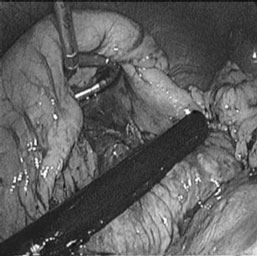

Utilização do ultra-som laparoscópico para análise do pâncreas e localização do Wirsung que foi puncionado, guiado pelo mesmo (figuras 2 e 3). Abertura longitudinal do Wirsung com lâmina fria de número 11. Esta abertura foi complementada no sentido de sua cauda e posteriormente de sua cabeça com o bisturi ultra-sônico. Durante a abertura do ducto pancreático principal foram identificados alguns cálculos que foram retirados da cavidade com uma pinça reta que os trazia para dentro do redutor (figura 4).

Figura 4 - Cálculo retirado do Wirsung sendo apreendido pela pinça a fim de ser retirado da cavidade abdominal.